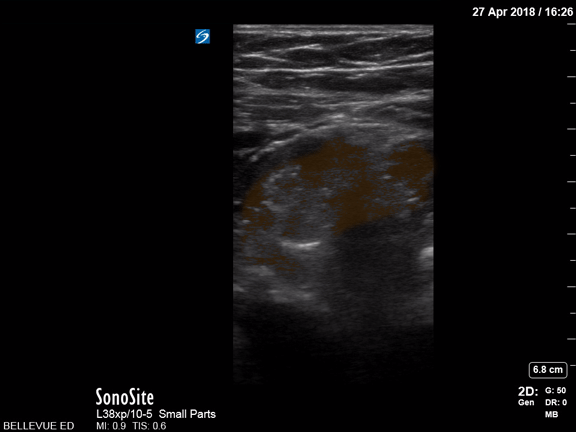

Bowel-GI - Large Bowel - Colorized

Large Bowel Orange - Large bowel lumen Images: Dr. Lindsay Davis, Dr. Hannah Kopinski. Image Editing: Michael Amador and Dr. Matthew Riscinti